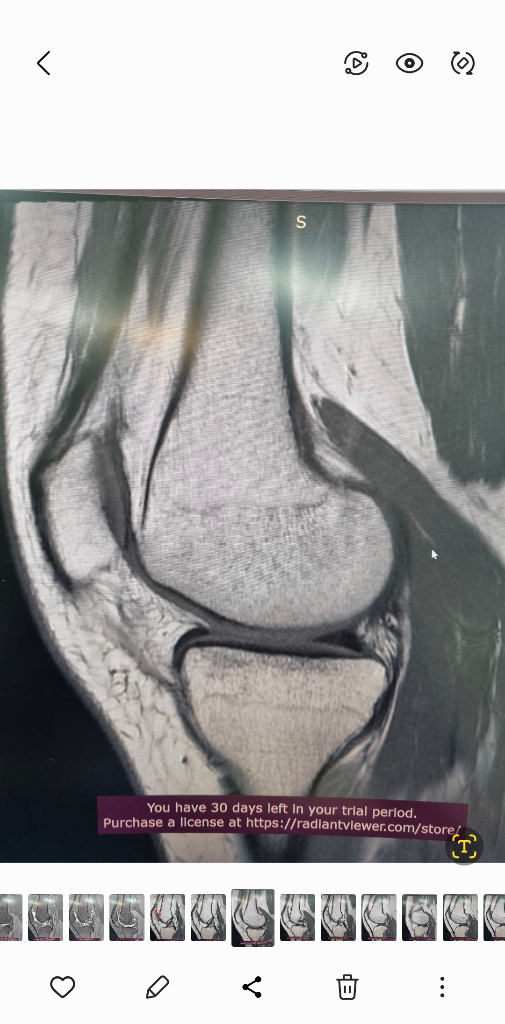

MRI는 신호가 다른 다른 사진들이 있을겁니다.

그런걸 종합적으로 판단해야 정확히 알수 있습니다.

검사한 병원에 판독요청하세요.